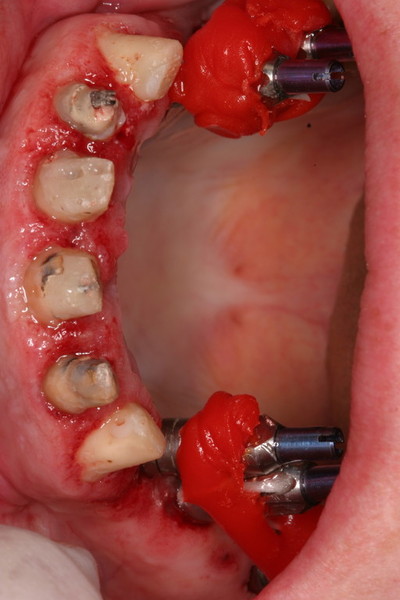

Tratamiento de la enfermedad Periodontal. Con cirugías periodontales de Widman modificado por la técnica de Ramfjiord por cuadrantes, Raspajes curetajes y alisado radicular.

Relleno de los defectos óseos verticales, con material de injerto aloblástico.

Tallado de las piezas remanentes , tratamientos endodónticos y ferulización con provisionales.

Tratamiento de la enfermedad periodontal como en el maxilar.

Injerto de mentón para conseguir aumento vertical y solucionar la recesión gingival. Fijación del injerto óseo con tornillo de osteosíntesis.

Provisionales, tratamientos endodónticos, ferulización con provisionales.